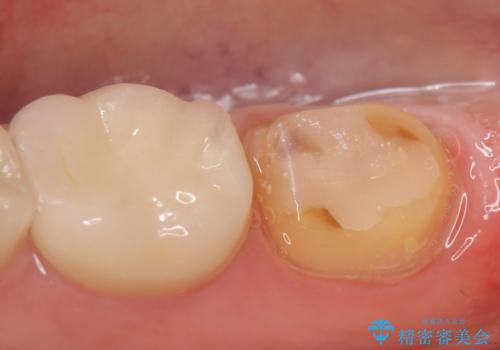

- 右下の奥歯でものを咬むと違和感があるので診て欲しいといらっしゃった方の症例です。

右下6は神経が死んでいたため根管治療を行い、オールセラミッククラウンによる補綴を行いました。

右下7は冷たいものがしみていたため、銀歯を除去後、オールセラミッククラウンによる補綴を行いました。